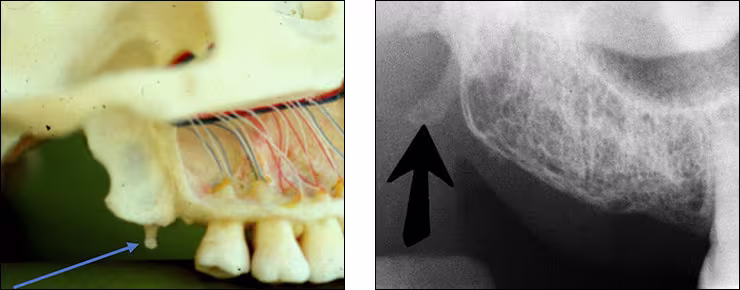

Hamular process – The hamular process or pterygoid hamulus is a tiny finger or hook-like projection of bone that extends inferiorly from the medial pterygoid plate (Figures 20 A&B). This bilateral radiopacity occasionally appears on maxillary molar periapical images and molar bitewings when the receptor is positioned sufficiently posterior to record it.

Figures 20 A&B: Pterygoid Hamulus